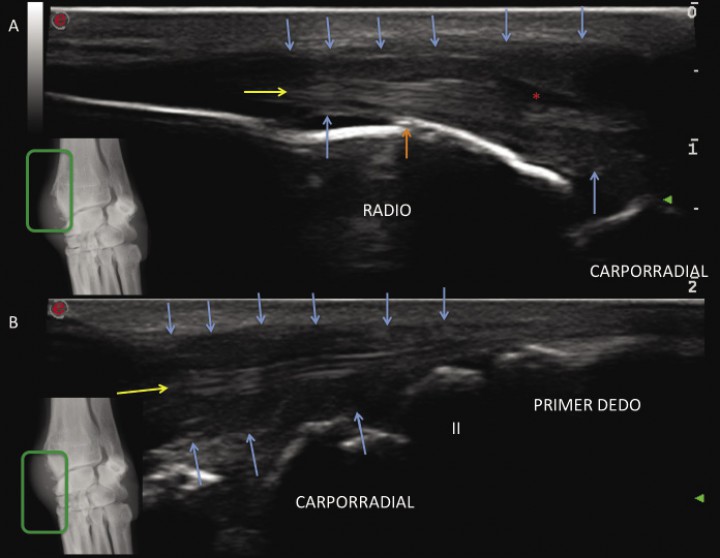

Para corroborar nuestras sospechas de afección del tendón abductor pollicis longus se realiza una ecografía con transductor lineal de alta frecuencia (Esaote MyLab Class C, 4- 13 MHz). Sobre un corte longitudinal de la cara dorsomedial del radio distal (Fig. 3) apreciamos marcado engrosamiento del tendón abductor pollicis longus sin pérdida del patrón de fibras (flecha amarilla) así como del tejido periférico que lo engloba (flechas azules), con presencia de efusión dentro de la vaina tendinosa (asterisco rojo). La superficie ósea se aprecia irregular, indicando reactividad del hueso cortical subyacente (flecha naranja). No se observan indicios de inflamación intrarticular o presencia de osteofitosis en la articulación radiocarpiana, intercarpiana o carpometacarpiana (Fig. 3). Estos hallazgos se observan de manera clara mediante cortes transversales a lo largo del tendón (Fig. 4), donde se puede identificar la neoformación ósea “englobando” el tendón abductor especialmente en la inserción de la vaina tendinosa al radio distal.

<p>Imagen ecográfica en corte longitudinal mostrando el recorrido del tendón abductor <em>pollicis longus</em> (flecha amarilla) sobre el radio distal (A) y el carpo-metacarpo medial (B) donde se inserta sobre el primer metacarpiano. Obsérvese el engrosamiento de la vaina tendinosa (flechas azules), la proliferación ósea cortical (flecha roja) y la efusión peritendinosa (*).</p>

Imagen ecográfica en corte longitudinal mostrando el recorrido del tendón abductor pollicis longus (flecha amarilla) sobre el radio distal (A) y el carpo-metacarpo medial (B) donde se inserta sobre el primer metacarpiano. Obsérvese el engrosamiento de la vaina tendinosa (flechas azules), la proliferación ósea cortical (flecha roja) y la efusión peritendinosa (*).